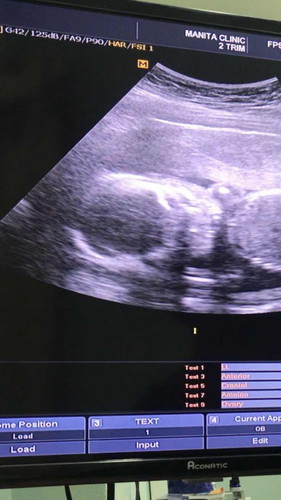

บ้านนี้ได้ลูกสาวค่ะ

24w จิ๋มน้อยของหม่ามี้